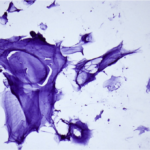

Cytopathology

Cytopathology Home

Picture Atlas